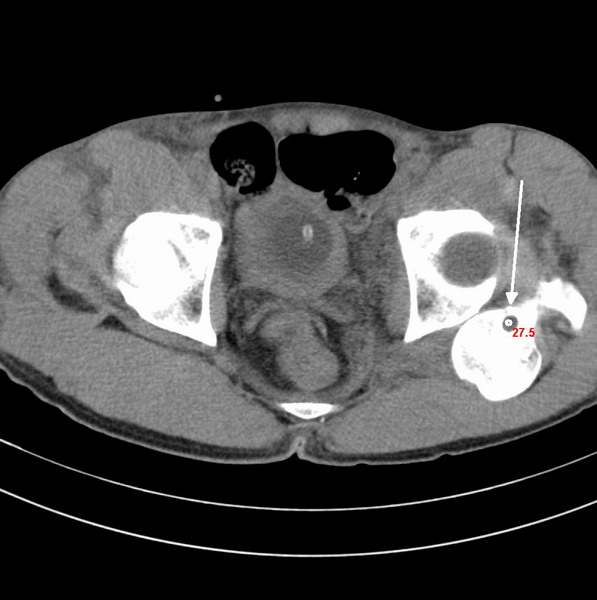

标题: CT18589:股骨头囊状阴影怎么下结论?

男、53

股骨头内的囊状阴影怎么下结论?

左髋关节脱位,其内圆形低密度影,考虑为股骨头疝窝

左侧髋关节后脱位;左侧股骨头疝窝。

左侧髋关节后脱位;左侧股骨头疝窝

二、影像学表现

x线平片和ct上多表现为位于股骨头基底和股骨颈近段前侧皮质下、股骨颈中轴线外侧的圆形或卵圆形透亮区或软组织密度灶,边界清楚,多伴有薄层硬化缘。病灶最大径线通常<10 mm。病灶或相邻上下层面上相邻皮质大多可见与病灶相连的局限性裂隙样缺损,可作为诊断此病的特异性征象。病灶内通常为纤维结缔组织和(或)液体。内为液体时,病灶呈均匀长t1、长t2信号。纤维结缔组织和液体同时存在时,病灶于t1wi上呈低信号,t2 wi上呈不均匀高信号。